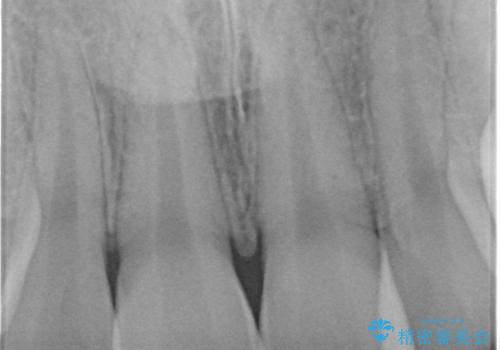

- 前歯を良くしたい(綺麗にしたい)との事で来院。

前歯のがたつきを治す治療プランとして

1 矯正を行い歯並びを良くする。(費用と時間がかかる)

2 セラミッククラウンで見た目を良くする(短時間で終わるが歯の向きを無理やり変えるために便宜的に歯の神経を抜く必要がある。健康な歯を削る)

のご提案をしたところ2のプランを選択されたのでセラミック治療を行いました。

- ジルコニアクラウンスペシャル・仮歯 16.5万円×2 精密根管治療(イニシャルトリートメント)・ファイバーコア 8.8万円費用は治療当時の料金となります

根管治療の注意事項(リスク・副作用など)

- 根管治療により類似の全ての症例の問題が解決するわけではなく、症例はあくまでも一例です

- 根管治療により痛みや腫れがひかない事や、術後に痛みや腫れが生じる事、治療によるファイル破折やパーフォレーションなどの偶発症、術後の歯根破折を生じる可能性もあります

- 自費診療(保険適用外)となります